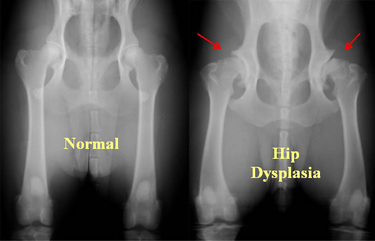

Canine hip dysplasia (CHD), or developmental dysplasia of the hip (DDH), is a degenerative disease that causes a hip deformity in dogs.

Hip dysplasia is a common skeletal condition, seen in dog breeds of all sizes, however more prominent in large or giant breeds. This condition causes the ball and socket joint of the hip to grind and causes deterioration over time due to uniform growth not occurring during development.

The only accurate way to diagnose dysplasia is to see a vet.